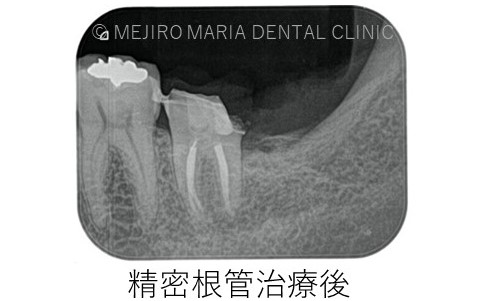

左下7番の診断は歯髄壊死が起因して起こる根尖性歯周炎であったため、まず左下7番に対して根管治療を行うことが必要でした。

しかし、当院で精密根管治療を施しましたが完全な疼痛の除去は行えませんでした。

根管の形態は非常に複雑で、根管の内部を完全に無菌化することは現在のいかなる歯科治療でも不可能です。これを歯内療法では「根管治療の限界」と言います。

その場合、もう一度根管治療を行っても根管内の細菌を無菌化できるわけではなく、更に歯質を大きく削ることになるため、外科的歯内療法(歯根端切除術)にて問題を解決します。